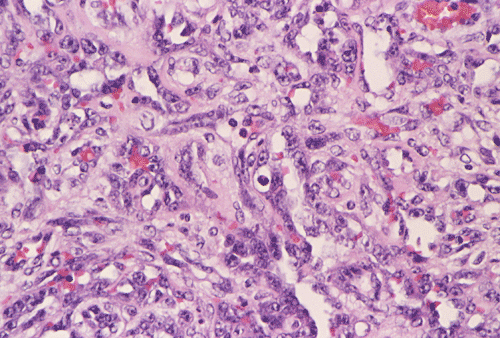

The tumor appears to be centered on the dermis and does not involve breast parenchyma in the sections examined A (not shown). On low-magnification (Panel A, B and F), the lesional tissue is a highly cellular and vascular tumor in the dermis. The large areas of hemorrhage ("blood-lake") and dilated vascular channels (Panel A, and F) probably correspond to the "red nodules and yellow patches" on physical examination. Although the tumor extends deeply into the subcutaneous tissue (not shown here), there is no evidence of invasion in to the epidermal layer (Panel A, B and F). The histology of this tumor varies in different areas. In some areas, it appears as a densely packed spindle cell tumor with exuberant and irregular and anastomosing vascular channels (Panel B, C, and D). The endothelial cells protrudes into the vascular channels and had enlarged, hyperchromatic nuclei with  prominent nucleli. In another area, the lesion contains numerous ectactic and anastomosing vascular channels (Panel F, G, H, and I). Pleomorphic changes are also prominent in the vascular cells in these areas. On immunohistochemistry, the tumor cells are immunoreactive for CD31, CD34 (not shown).

The most distinctive histologic feature in angiosarcoma is the formation of irregular, anastomizing vascular channels lined by plump, hyperchromatic, and anaplastic endothelial cells. These vascular channels proliferate and infiltrate the glandular breast tissue, fat and subcutaneous tissue.  Low-grade lesions usually have only rare mitotic figures. Increased mitotic activity in an otherwise low-grade angiosarcoma may suggest the presence of a high-grade lesion in adjacent tissue.  Intermediate-grade lesions have an increased amount of endothelial tufting and papillary formations within the irregular vascular channels and these are associated with increased numbers of mitoses. While the anastomizing vascular channels are characteristic of areas with low- or intermediate- grade cytologic features, solid sheets of spindle cells with minute, slit-like channels not filled by red blood cells are common in high-grade areas. In addition, high-grade angiosarcoma are marked by numerous mitotic figures in all parts of the tumor, the presence of “blood lakes”, and necrosis.  In most tumors the high-grade portion comprises the core of the tumor and the better-differentiated portion forms the infiltrative border of the lesion 3.